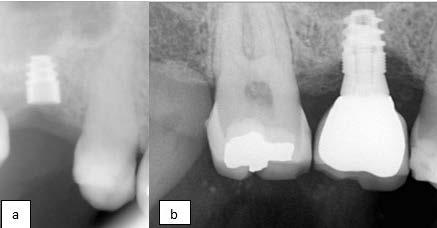

Se planteó la utilización de cerámica feldespática e-max de la casa comercial Ivoclar Vivadent, en la presentación de bloques para la realización de las coronas totales en los OD

11, 12 y 13 mediante técnica CAD/ CAM, en su versión HT, color A2. Por otro lado, las otras 2 coronas de los OD 21 y 22 fueron confeccionadas con disco de zirconia Zahndent en tono A2. Estas fueron puestas a prueba mediante la aplicación Adobe Photoshop, con ayuda de una fotografía de las coronas tomada antes de su cementación definitiva, y una segunda medición con las coronas ya cementadas, únicamente se realizó el análisis en los OD 11 Y 21, los cuales fueron cementados con cemento translucido Multilink Speed de Ivoclar Vivadent, se tomaron fotografías con cámara profesional Cannon T8 y lente macro 100mm. Es importante mencionar que decidí utilizar cemento dual translucido para evitar alteración en el color de las coronas ya cementadas, con el fin de obtener mediciones puntuales de color y determinar las cantidades de pigmento que hay en cada corona mediante un fondo negro y así poder corroborar que se logró un buen mimetismo. El tiempo estimado para el procedimiento fue de 5 citas.

Figura 1. Coronas antes de su cementación (Francisco Javier Méndez Landa 2024).

porcentaje de 0 a 100, obteniendo el porcentaje exacto de cada uno de esos colores, que una vez mezclados obtenemos el tono real de las coronas (Figura 1).

Se realizó la medición del color de las coronas mediante una fotografía en formato RAW en fondo negro (Figura 2).

Se muestra un análisis del proceso de medición de color de las coronas antes de su cementación y cómo se obtuvieron los resultados, mediante la aplicación Adobe Photoshop (Figura 3).

Se muestra una fotografía del análisis de los incisivos centrales, los cuales fueron confeccionados: el órgano

dentario 11 con disilicato de litio y el órgano dentario 21 con zirconio.

Resultados

Los resultados obtenidos fueron que, en promedio, sí existe variación de los pigmentos en cuanto a la medición de la mezcla de los 3 colores antes de ser cementadas las coronas del canino, incisivo central y lateral superior derechos; las cuales fueron confeccionadas con e-max, en una escala de 0 a 255 que arroja la aplicación Adobe Photoshop obteniendo los siguientes valores: en cuanto al canino superior derecho, se obtuvieron valores del color rojo: 195, del color verde: 179 y del color azul: 157. Del incisivo lateral izquierdo superior se obtuvo del color rojo: 197, del color verde: 181 y del color azul 161. Del incisivo central superior izquierdo se obtuvo del color rojo: 195, del color verde: 180 y del color azul: 158. En

cuanto las otras 2 coronas restantes, las cuales fueron confeccionadas con zirconio del incisivo central superior derecho obtuvimos del color rojo: en promedio 196, del color verde: 181 y del color azul: 161. Del incisivo lateral superior derecho del color rojo obtuvimos: 187, del color verde: 174 y del color azul: 156.

Se realizó un segundo análisis con las coronas ya cementadas en boca, únicamente de los incisivos centrales superiores, ya que uno fue confeccionado con disilicato de litio y el otro con zirconio. En este caso obtuvimos como resultado en la corona de disilicato de litio: del color rojo: 172, del color verde: 148 y en cuanto al color azul: 123. En la corona de zirconio obtuvimos del color rojo: 171, del color verde: 143, y del color azul: 119; en la escala de 0 a 255 que arroja la aplicación de Adobe Photoshop.

Podemos afirmar que también hubo variación y a pesar de utilizar 2 tipos de cerámicas diferentes, se logró obtener un buen mimetismo, dando como resultado un resultado satisfactorio para la paciente.

Se muestra un análisis comparativo de las coronas de los incisivos centrales, las cuales fueron confeccionadas, una con disilicato de litio, y la otra con zirconio.

Figura 3. Coronas ya cementadas.

Tabla 2. Análisis de las coronas ya cementadas. Se muestra un análisis comparativo de las coronas de los incisivos centrales, las cuales fueron confeccionadas, una con disilicato de litio y con zirconio.